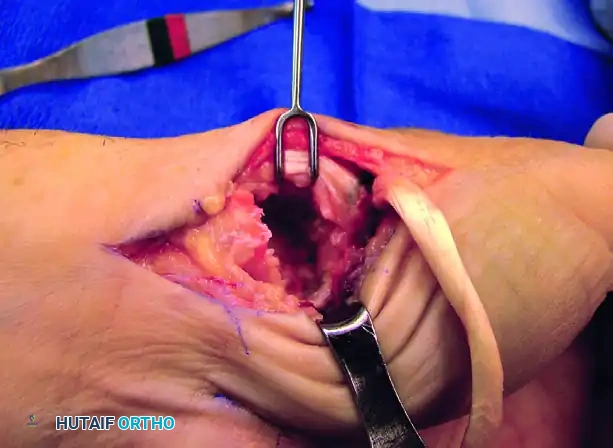

Trapezial Excision and Metacarpal Preparation

- Trapeziectomy: After exposing the joint through a volar incision along the FCR path and reflecting the thenar muscles, perform a complete excision of the trapezium. Care must be taken to protect the underlying FCR tendon during piecemeal or en bloc resection.

- Bone Tunnel Creation: Using a 4-mm rough burr, create holes through the base of the thumb metacarpal, directing them proximally and radially. Connect these holes using a series of curets (usually up to a No. 2) to form a smooth, continuous tunnel.

Figure A: Holes made in the thumb metacarpal base following trapeziectomy.

Intraoperative view of the trapezial void and preparation of the metacarpal base.